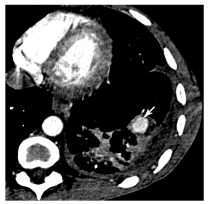

Fig. 92.3. Scanner thoracique avec injection de produit de contraste iodé.

Hémoptysie dans un contexte de tuberculose active : formation arrondie lobaire inférieure gauche se rehaussant (flèche) et correspondant à un anévrisme de Rasmussen développé à partir d’une artère pulmonaire.

Source : CERF, CNEBMN, 2022.